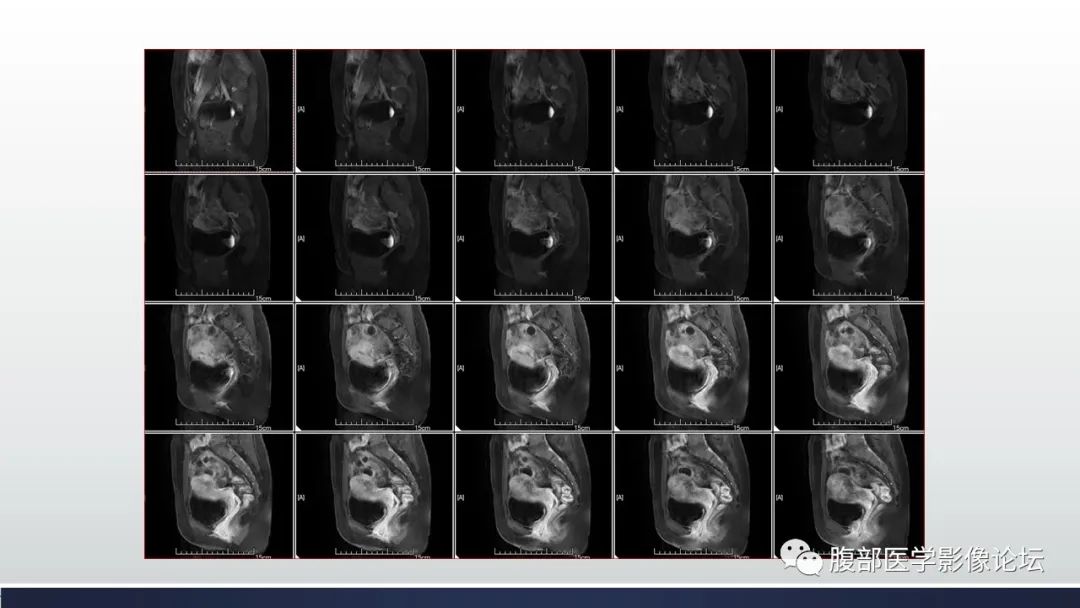

【病例】子宫内膜透明细胞癌1例MR-5

【病例】子宫内膜透明细胞癌1例MR-6

【病例】子宫内膜透明细胞癌1例MR-7

【病例】子宫内膜透明细胞癌1例MR-8

【病例】子宫内膜透明细胞癌1例MR-9